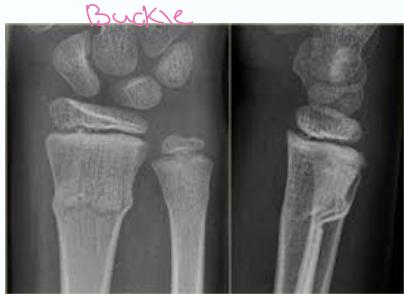

- Torus (buckle) - Compression on one side